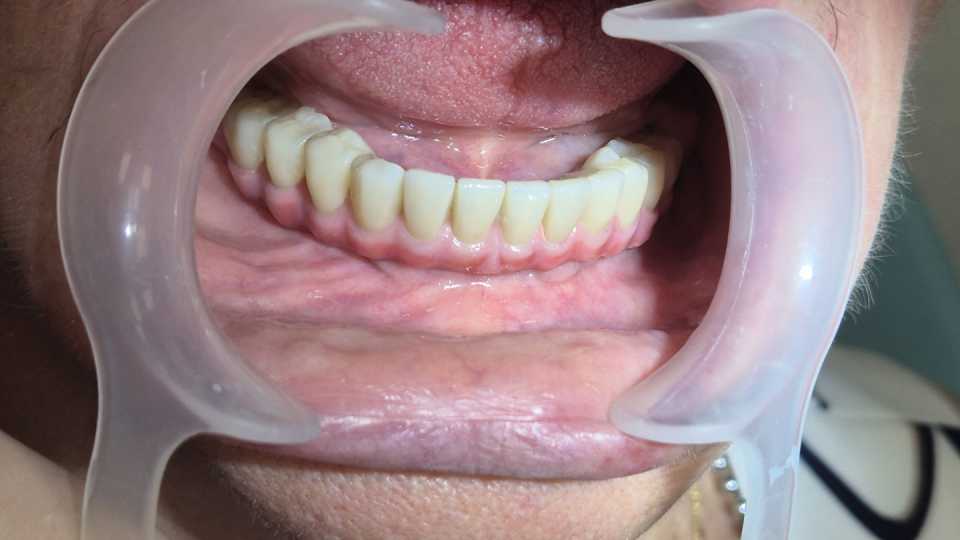

Pacienta, în vârstă de 77 de ani, purtătoare veche de proteză mobilă la nivel mandibular, a dezvoltat o resorbție osoasă severă, ceea ce a dus la dificultăți majore în masticație și imposibilitatea purtării protezei. Se prezintă cu dorința de a beneficia de o lucrare fixă la nivelul mandibulei.

Cu ajutorul a 4 implanturi dentare Mega-Gen AnyRidge, inserate interforaminal (tehnica All-on-4), realizăm o lucrare din ceramică pe suport de titan, formată din 12 elemente, înșurubabilă pe suport multiunit.